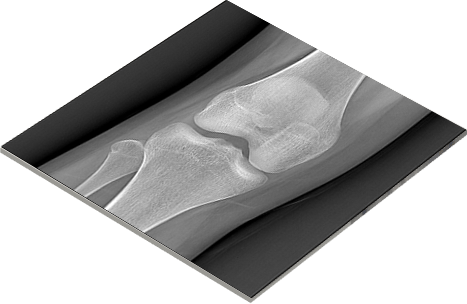

远程影像同步操作

实现在不同地点,使用不同设备同步浏览图像,一方操作,其他客户端可以同时浏览相同的影像:包括影像的查看,操作,测量等功能